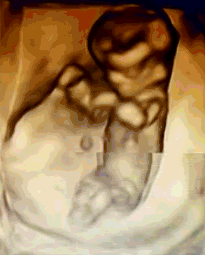

NT是胎儿颈部半透明膜的缩写,是10~13孕周围绕在胎儿颈项后部流动性的半透明蛋白膜。它的厚度与胎儿DS缺陷正相关,并可以通过超声成像测量。NT检查便于及早发现唐氏儿、先天性心脏病和其他结构畸形的胎儿,并及时予以干预。

美琳达超声科引进多台美国GE-E10、美国GE-E8等系列机器,能够提高细节分辨率,实现在扫描同时即刻呈现胎儿标准生长曲线和相应测量数据,满足从早孕期研究到复杂胎心的全程早期检查和诊断,不存在射线、光波和电磁波等方面的辐射。通过四维立体成像,清晰并动态记录宝宝在子宫内的活动和成长历程